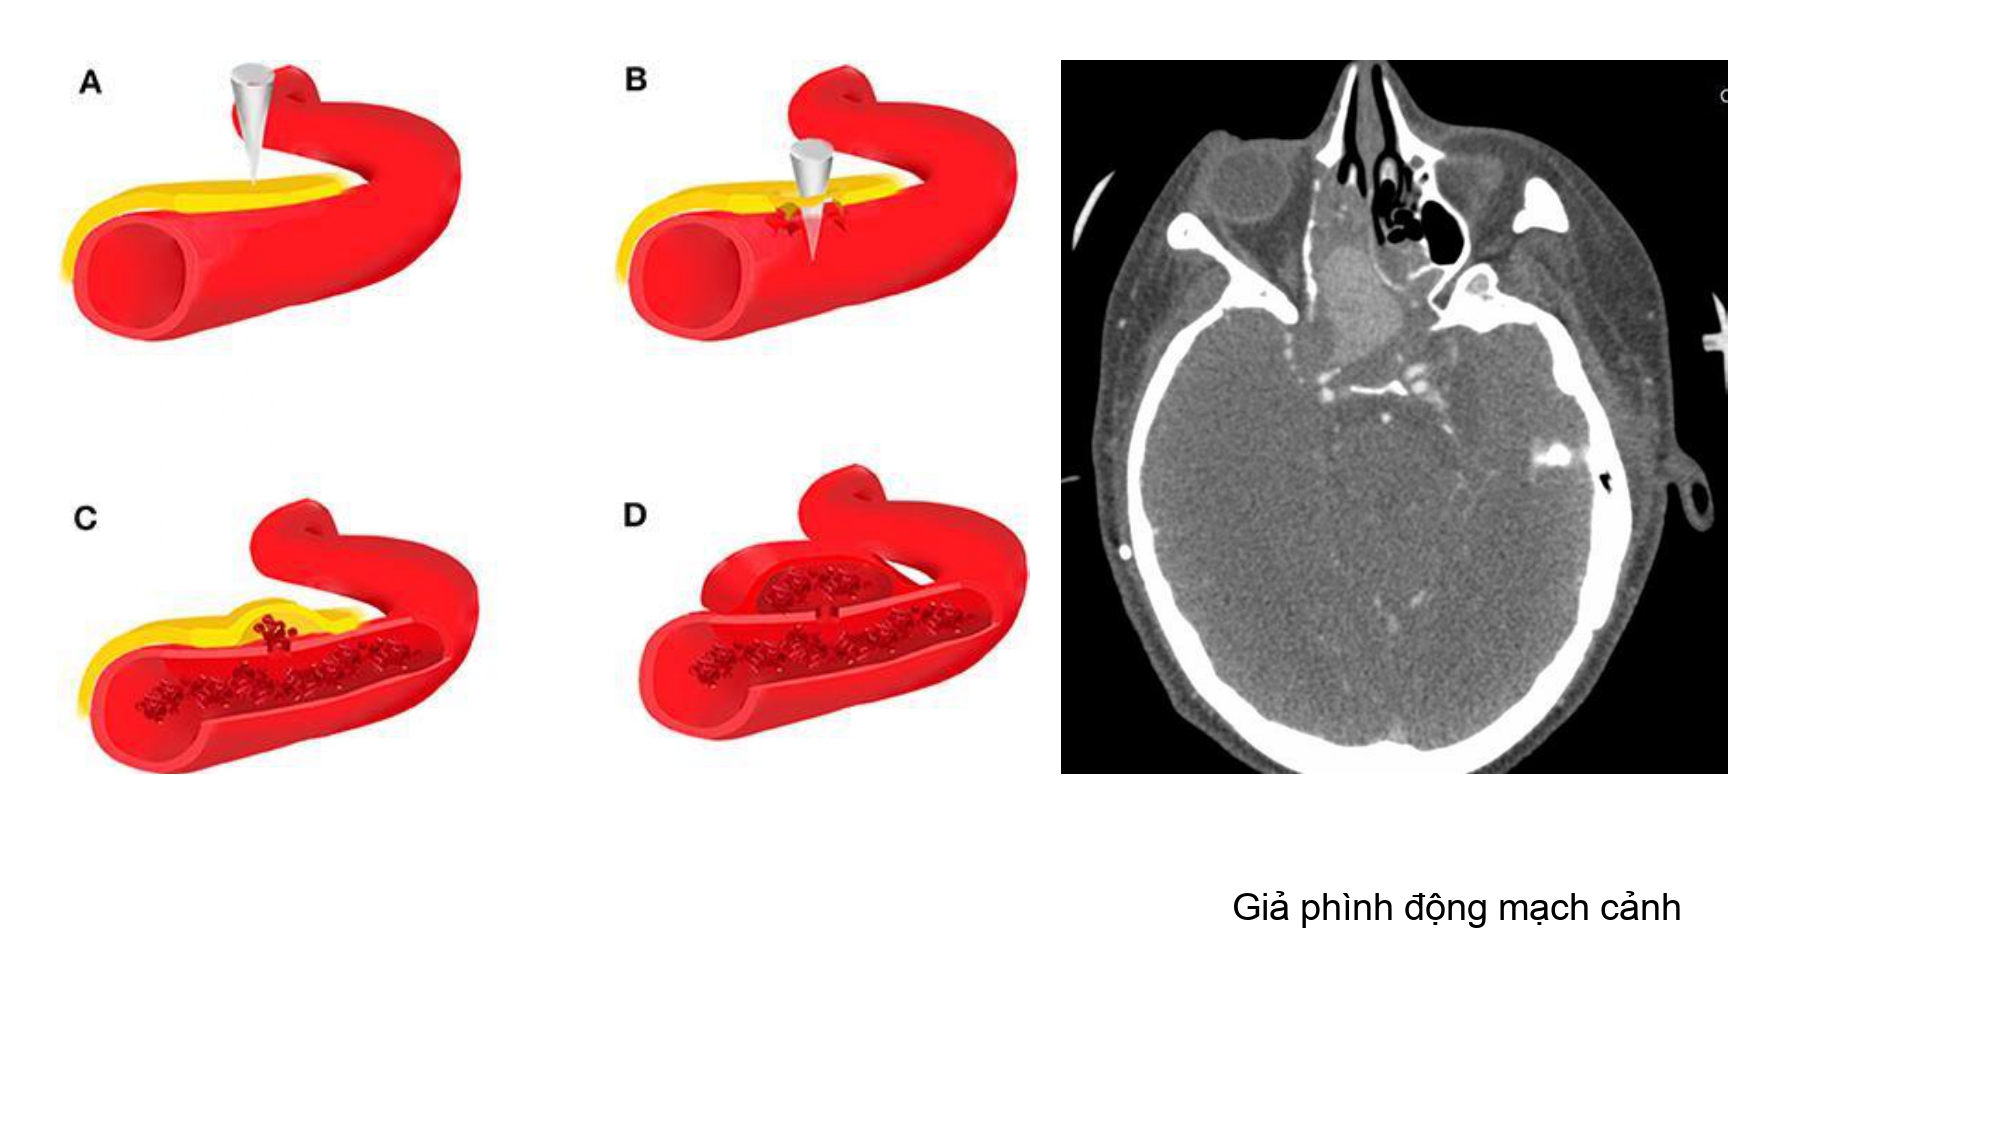

| 13:30 - 14:10 | Surgical management of skull base trauma Endovascular Management of Post-Traumatic Intracranial Vascular Lesions | Assoc. Prof. Nguyen Trong Yen Dr. Nguyen Ngoc Cuong | |

| 14:10 - 15:10 | DEBATE 2 | Recurrent chronic subdural hematoma– surgical or endovascular intervention? Surgical: Assoc. Prof. Duong Dai Ha Endovascular: Assoc. Prof. Le Thanh Dung | Moderator: Prof. Christian Matula Assoc. Prof. Duong Dai Ha | |

| 15:10 - 16:10 | Interactive Case Demonstration and Discussion II: ~20 minutes each, (5 minutes presentation followed by 15 minutes discussion) Practicals: How I am doing it? Participants present case presentations about how they do it? The faculty comment on and discussion. 1. Endoscopic approach in post-traumatic CSF leakage - Dr. Nguyen Thanh Xuan 2. Endovascular approach in CCF - Assoc. Prof. Le Thanh Dung | Prof. Christian Matula International & local faculties Participants | |